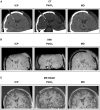

Cerebral microdialysis may be used in patients with severe brain injury to monitor their cerebral physiology. In this article we provide a concise synopsis with illustrations and original images of catheter types, their structure, and how they function. Where and how catheters are inserted, their identification on imaging modalities (CT and MRI), together with the roles of glucose, lactate/pyruvate ratio, glutamate, glycerol and urea are summarized in acute brain injury. The research applications of microdialysis including pharmacokinetic studies, retromicrodialysis, and its use as a biomarker for efficacy of potential therapies are outlined. Finally, we explore limitations and pitfalls of the technique, as well as potential improvements and future work that is needed to progress and expand the use of this technology.